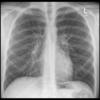

Normal PA

24 yo male

Date: 06/08/2016

Views: 6526